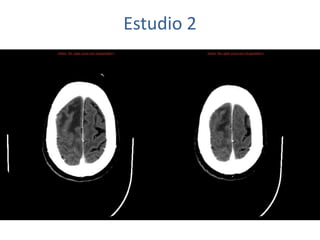

Estudio 2

• Estudio sin y con contraste, con reconstrucciones sagitales y coronales

del estudio con contraste.

Se observa una lesión ocupante de espacio en lóbulo frontal derecho que

presenta un tamaño de 18 x 32 x 22 mm (cc x ap x tr), bilobulada, no del

todo bien delimitada, con realce en anillo irregular, con hipocaptación

central, probablemente por necrosis, y asociada a un extenso edema

vasogénico con efecto masa tanto sobre los surcos de la convexidad

como sobre la cisterna insular, el sistema ventricular y la línea media,

esta última con un desplazamiento de 5 mm a la altura del septo

interventricular.

No se aprecian otras lesiones focales intra o extraaxiales de significación

patológica.

Habría que considerar como primera posibilidad que se tratase de una

lesión metastásica, por bien un tumor primario, aunque no se puede

descartar otras opciones, sin imprescindible correlación con la clínica y

con sus antecedentes.